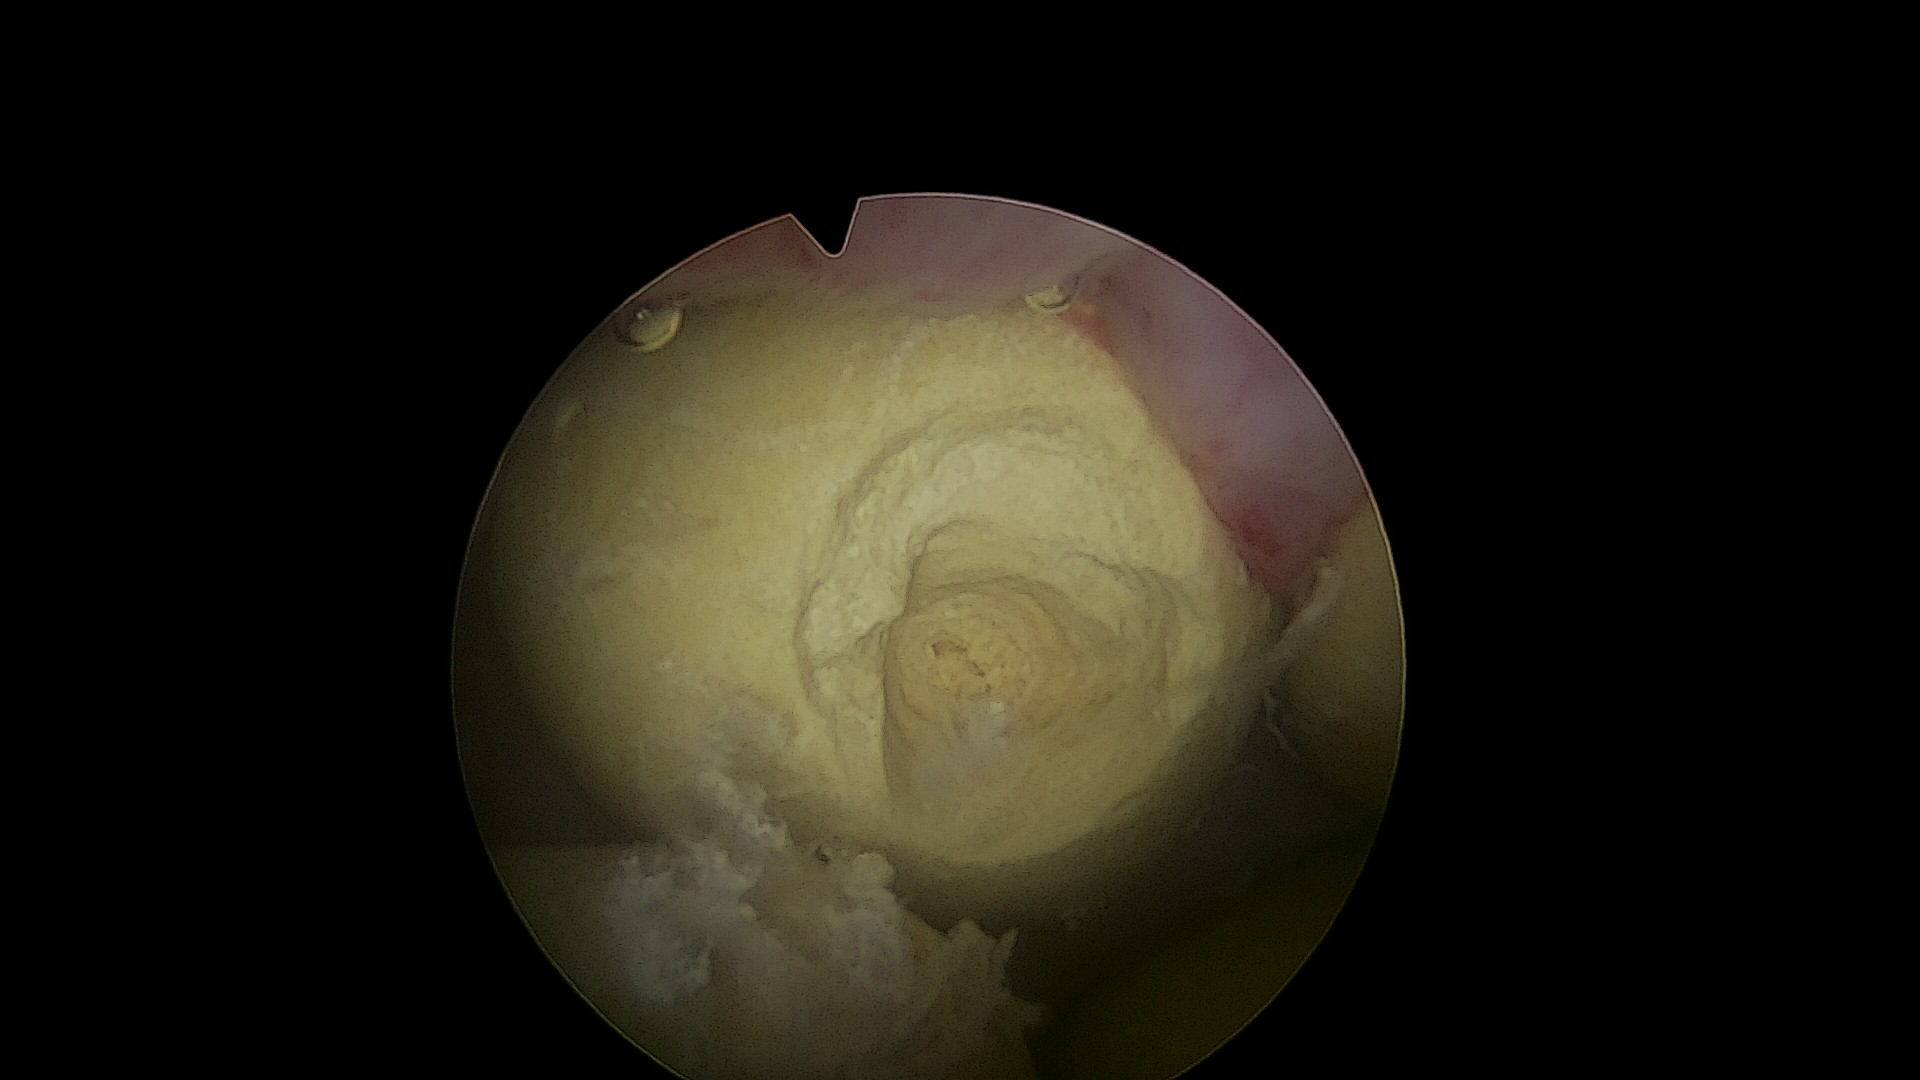

3.钬激光碎石系统

泌尿系统结石的钬激光碎石